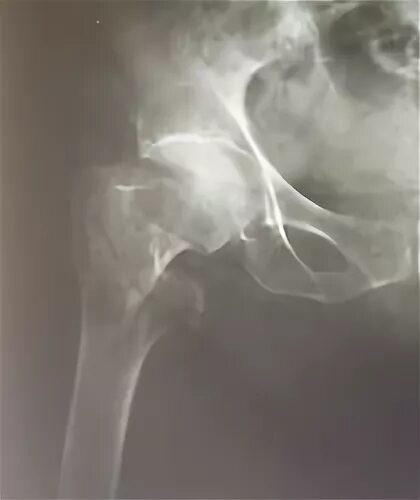

Чрезвертельный перелом без операции